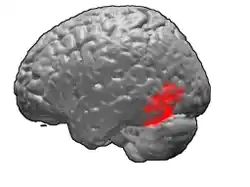

Brodmann area 37, or BA37, is part of the temporal cortex in the human brain. It contains the fusiform gyrus which in turn contains the fusiform face area, an area important for the recognition of faces.

This area is also known as occipitotemporal area 37 (H). It is a subdivision of the cytoarchitecturally defined temporal region of cerebral cortex. It is located primarily in the caudal portions of the fusiform gyrus and inferior temporal gyrus on the mediobasal and lateral surfaces at the caudal extreme of the temporal lobe. Cytoarchitecturally, it is bounded caudally by the peristriate Brodmann area 19, rostrally by the inferior temporal area 20 and middle temporal area 21, and dorsally on the lateral aspect of the hemisphere by the angular area 39 (H) (Brodmann-1909).[1]